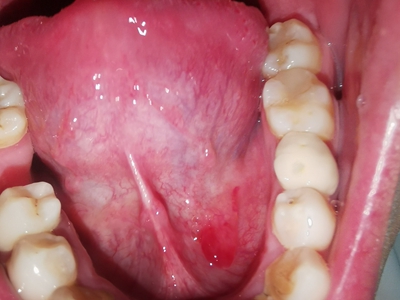

舌下腺囊肿舌头下面长了一个圆形肿块图

舌下腺囊肿位于舌底一侧,表现为圆形、光滑、柔软的肿块,直径约3cm大小,紧贴下牙,囊肿壁薄,呈浅紫蓝色,破裂并流出黏稠的液体。